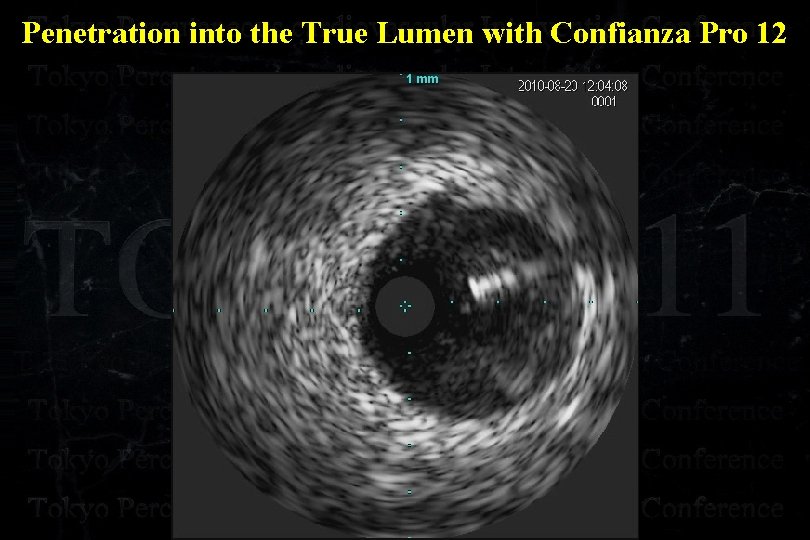

Penetration into the True Lumen with Confianza Pro 12

Penetration into the True Lumen with Confianza Pro 12

Penetration into the True Lumen with Confianza Pro 12